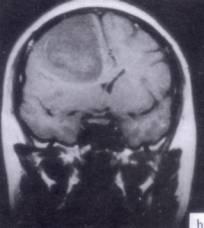

问题 病历摘要:??患者男性,52岁。头痛伴呕吐2月,呕吐呈喷射性。既往身体健康。体检:神清,表情淡漠,反应迟钝,双眼底视神经乳头明显水肿,左鼻唇沟稍浅,左腹壁反射减弱,左上下肢肌力4级,左Babinski征(-)。 根据病史、MR结果,首先考虑哪种诊断?提示:患者行头颅?MR检查(见图)

选项 A.右额叶胆脂瘤 B.右额叶转移瘤 C.右额叶胶质瘤 D.右额叶淋巴瘤 E.右额叶脑膜瘤 F.右额叶脑脓肿 G.右额叶炎性肉芽肿

答案 C